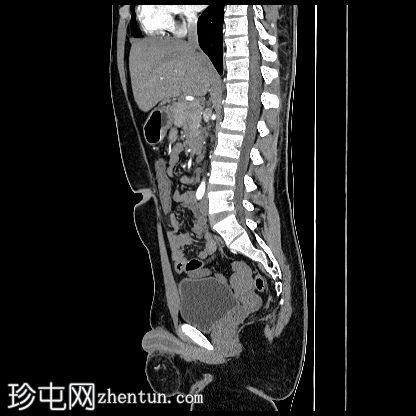

CT

轴位

平扫

阴茎:发育良好。阴茎海绵体和尿道海绵体均存在。

阴囊:双侧均存在,但空虚。

左侧腹股沟深环可见一裂隙,大网膜脂肪由此突出至左侧阴囊。裂隙大小约20毫米。

盆腔左侧可见一形态良好的子宫样结构(57 x 17毫米),开口于前列腺尿道。

右侧睾丸位于盆腔右侧,膀胱与直肠之间。大小:56 x 29 毫米。

左侧睾丸位于盆腔中线左侧,膀胱上方,子宫底旁。该结构附着于从左侧腹股沟管延伸出的索状结构上。大小:38 x 22 毫米。